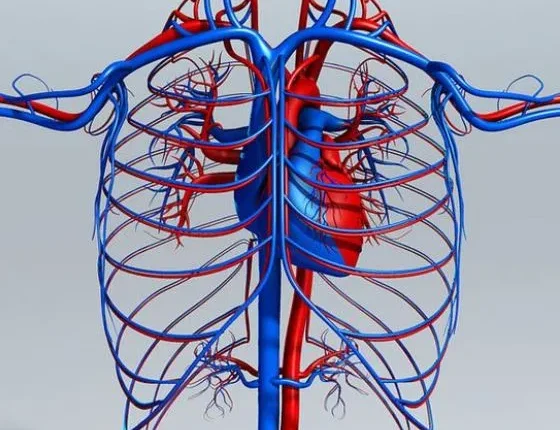

Το κυκλοφορικό σύστημα ή το καρδιαγγειακό σύστημα αποτελείται από την καρδιά, τις φλέβες, τις αρτηρίες και τα τριχοειδή αγγεία. Αυτό το σύστημα είναι υπεύθυνο για τη μεταφορά οξυγόνου και θρεπτικών ουσιών σε όλο το σώμα.